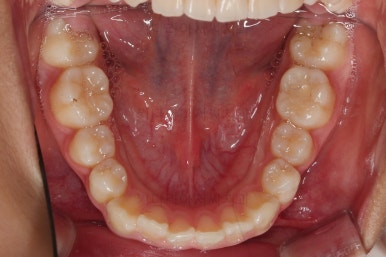

부산소아교정 초진 시 입안의 모습입니다.

윗니가 아랫니보다 많이 앞에 나와있고요.

심지어는 틈새가 벌어지기까지 했습니다.

윗니가 배열 되어있는 U자 형태(그릇 형태)가 아랫니보다 좁은 양상이고요.

이런 앵글씨 2급 부정교합에서는 아랫니가 윗니와 만나기 위해 솟구쳐서 과개교합(아래 앞니가 윗니 뒤쪽으로 깊숙히 올라가 있는 상태)이 나타나기까지 합니다.